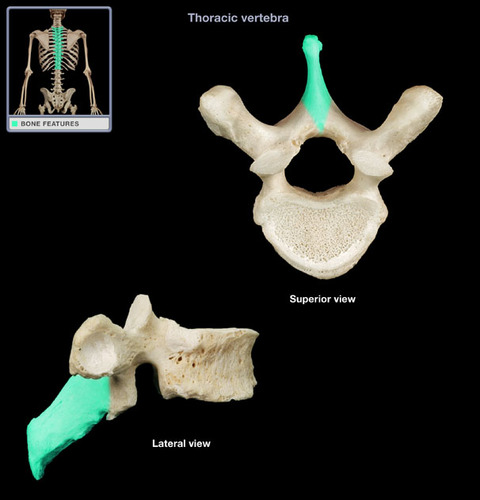

Thoracic Vertebrae

spinous process